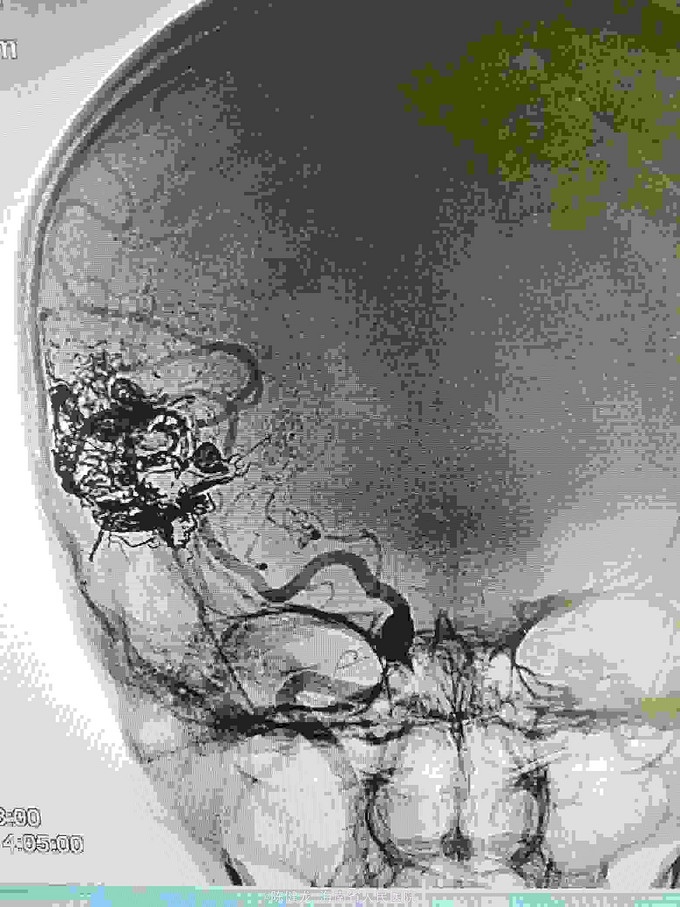

AVM

右颞大型AVM,大脑中主要供血。

右颞AVM

己进行二次治疗,拟近期内进行第三次治疗。争取80%至90%栓塞,残留部分伽玛刀治疗。